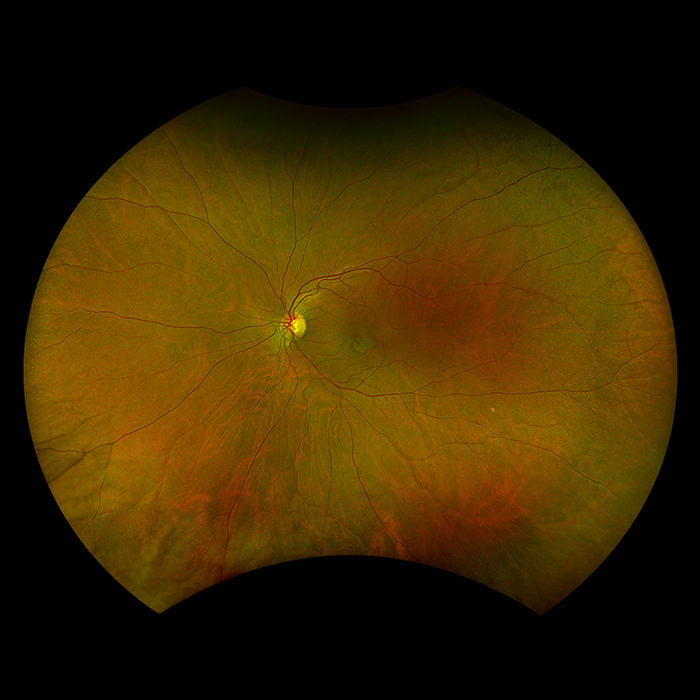

Silverstone RGB is redefining excellence in retinal imaging. It is the only device that captures true color, 200° optomap ultra-widefield images in a single shot, seamlessly integrated with guided swept-source OCT. For the first time, eye care professionals can access nine powerful imaging modalities in one system, each designed to image pathology anywhere in the retina.

optomap has been shown to enhance pathology detection, disease management, and to improve clinic flow. Now with nine retinal imaging modalities, including integrated, peripheral Swept Source OCT, Silverstone RGB facilitates examination of the retina from vitreous through the choroidal-scleral interface.

Silverstone RGB imaging modalities and image viewing options:

optomap Image Modalities

- color rgb

- color rg

- Sensory Retina

- Choroidal

- green af

- blue af

- fa

- icg

- SS-OCT